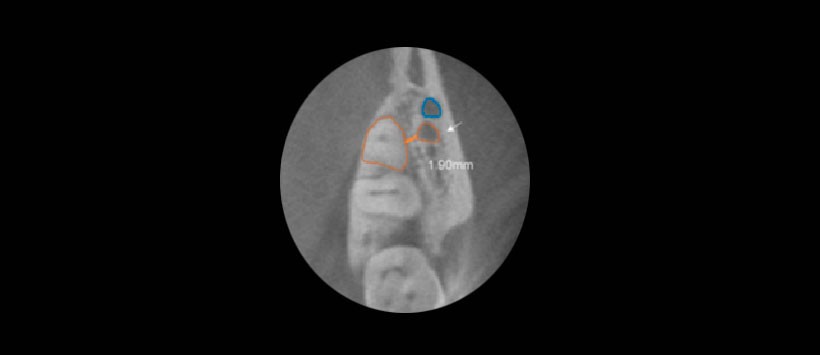

Sitio: El sitio de la bifurcación en relación con el tercer molar inferior. Se eligió una distancia de 2 mm desde la superficie de la raíz, en función del diámetro de una fresa de fisura quirúrgica comúnmente utilizada en la cirugía del tercer molar.

Figura 2: Distribución de canales bífidos que surgen del canal del nervio dental inferior en relación con el tercer molar inferior. Las ubicaciones de los canales se pueden describir como tipo 1, tipo 2d, tipo 2m y tipo 3.